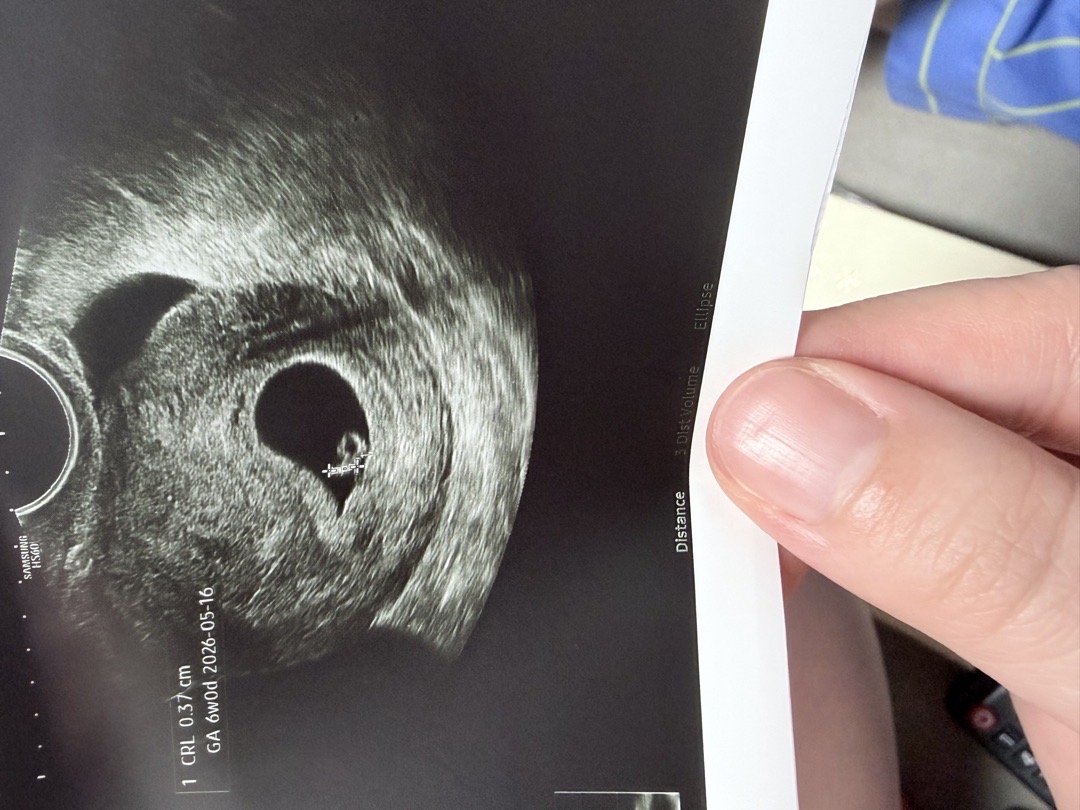

난황 각도법

난황으로 봤을 때 아들일까요 딸일까요?? 6주차입니다!